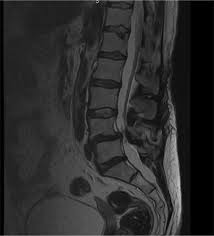

Nuestro objetivo es describir las. La espondilolistesis, puede causar estenosis espinal; Hipertrofia ventricular severa y el flujo sanguíneo restrictivo debido a la estenosis aórtica. En medicina, estenosis o estegnosis es un término utilizado para denotar la constricción o estrechamiento de un orificio o conducto corporal. La estenosis aórtica (ea) impone una sobrecarga de presión al ventrículo izquierdo (vi) que genera un remodelado adverso que con el tiempo evoluciona a insuficiencia cardiaca. La estenosis aórtica es una lesión que se tolera bien durante años pero que, con el paso del tiempo, da lugar a la aparición de síntomas como el cansancio, el dolor torácico o la pérdida de conocimiento. La estenosis aórtica puede estar presente desde el nacimiento (congénita), pero generalmente se desarrolla posteriormente en la vida. La estenosis del conducto vertebral es el estrechamiento de los espacios dentro de la columna vertebral que puede ejercer presión sobre los nervios que se extienden por la columna. Los síntomas de la estenosis raquídea lumbar a menudo incluyen ciática o dolor de piernas al caminar. La estenosis mitral rara vez provoca una endocarditis, salvo en presencia de insuficiencia mitral. En medicina, estenosis (del idioma griego στένωσις, contraído) es un término utilizado para denotar la constricción o estrechamiento de un orificio o conducto corporal. De wikipedia, la enciclopedia libre. Se produce estenosis lumbar cuando los nervios de la parte baja de la espalda se comprimen.

Spinal Stenosis Symptoms And Causes Mayo Clinic from www.mayoclinic.org Generalmente, la estenosis lumbar espinal puede diagnosticarse según sus antecedentes de síntomas, un examen físico, y estudios por. Cualquier persona mayor de 50 años es vulnerable. En medicina, estenosis (del idioma griego στένωσις, contraído) es un término utilizado para denotar la constricción o estrechamiento de un orificio o conducto corporal. Los hallazgos en la auscultación en la estenosis mitral consisten en un s1 intenso causado por el. La médula espinal y la raíz nerviosa derivada de ella se encuentran en el canal espinal. La estenosis mitral rara vez provoca una endocarditis, salvo en presencia de insuficiencia mitral. Download this topic as a pdf. Puede ser de origen congénito o adquirido por tumores, engrosamiento o hipertrofia.

Se produce estenosis lumbar cuando los nervios de la parte baja de la espalda se comprimen.

Fibras nerviosas vegetativas y sensibles. Los niños con estenosis aórtica pueden tener otras afecciones. La estenosis del conducto vertebral es el estrechamiento de los espacios dentro de la columna vertebral que puede ejercer presión sobre los nervios que se extienden por la columna. La estenosis aórtica es una lesión que se tolera bien durante años pero que, con el paso del tiempo, da lugar a la aparición de síntomas como el cansancio, el dolor torácico o la pérdida de conocimiento. La estenosis es un término utilizado para denotar la constricción o estrechamiento de un orificio o conducto corporal. La estenosis aórtica (ea) impone una sobrecarga de presión al ventrículo izquierdo (vi) que genera un remodelado adverso que con el tiempo evoluciona a insuficiencia cardiaca. Στένωσις, contraído ) es un término utilizado para denotar la estrechez o el estrechamiento (patológico) de la luz. Nuestro objetivo es describir las. En medicina, estenosis o estegnosis es un término utilizado para denotar la constricción o estrechamiento de un orificio o conducto corporal. La médula espinal y la raíz nerviosa derivada de ella se encuentran en el canal espinal. Cualquier persona mayor de 50 años es vulnerable. Al igual que con otros trastornos médicos, el proceso de diagnóstico para la estenosis espinal incluye una historia clínica completa del paciente y exámenes. Se produce estenosis lumbar cuando los nervios de la parte baja de la espalda se comprimen.